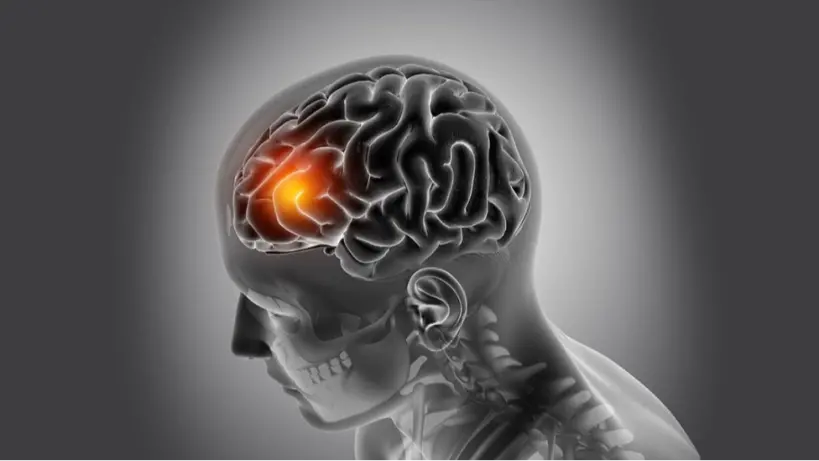

Ranked second most often occurring cause of mortality in the UAE after heart disease, stroke is a major health concern here. It is also a main contributor to long-term handicap. Usually resulting from a blood clot, strokes arise when blood flow to the brain is abruptly stopped, Rapid loss of brain cells resulting from this disturbance causes different symptoms affecting motor abilities, speech, and cognitive ability. Severe cases of stroke could result in either death or lifelong handicap.